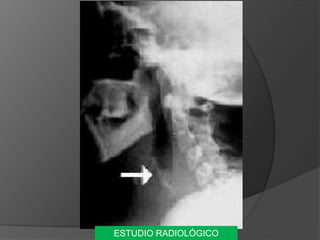

ESTUDIO RADIOLÓGICO

PRUBAS DE GABINETE MEDIRO CUANTIFICAR LA CAPACIDAD DE LA GLÁNDULA PARA ACUMULAR YODO (2 Y 24H.) 2 = 12% 24 = 20-50% GAMMAGRAFIA TIROIDEA